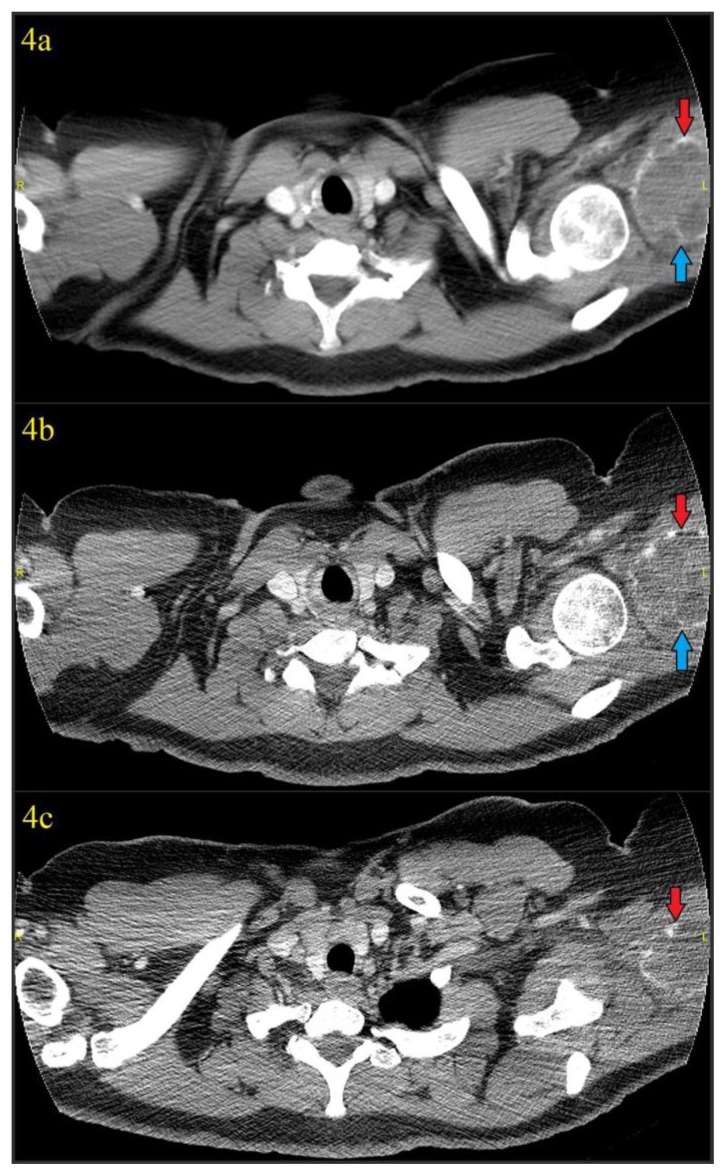

On CT, the mass again showed peripheral calcification. Central areas of hypodensity and a few calcified thin septations were also seen (figures 4a–4c). Magnetic resonance imaging (MRI) subsequently performed at an outside institution demonstrated a mass localized to the proximal triceps muscle and showed blood filled spaces of varying sizes with numerous fluid-fluid levels, T1/T2 hypointense septa, and a T1/T2 hypointense calcified rim with some septal enhancement (figures 5a–5f). There was no osseous involvement. A differential diagnosis of sarcoma and myositis ossificans was raised.

Figure 4.

41 year old female with a soft tissue aneurysmal bone cyst.

Findings: Figures 4a–4c: Axial images from non-contrast chest CT (thus the incomplete inclusion of the lesion) obtained 4 days after discovery of the calcified mass in the soft tissues of the left shoulder using soft tissue window which again showed the 7.0 (transverse) cm × 5.5 (anteroposterior) cm × 6.7 cm (craniocaudad) cm mass with rim calcification (red arrows) in the region of the posterior deltoid/upper triceps muscles. A thin calcified septation was also seen (blue arrows). Hypodense areas could be seen in the lesion, suggesting the underlying blood filled cystic spaces characteristic of an aneurysmal bone cyst.

Technique: CT was performed on a GE® 64-slice CT scanner. All images are from a non-contrast chest CT using soft tissue windows (width = 350, center = 40 for figure 4a, width = 400, center = 40 for figures 4b and 4c). Figure 4a is a 5mm slice using standard soft tissue algorithm, while figures 4b and 4c are high resolution 1.25mm slices from the edge-enhanced lung algorithm. 120 kVp was used with variable mAs, which ranged from 456 mAs to 457 mAs for the provided axial images.